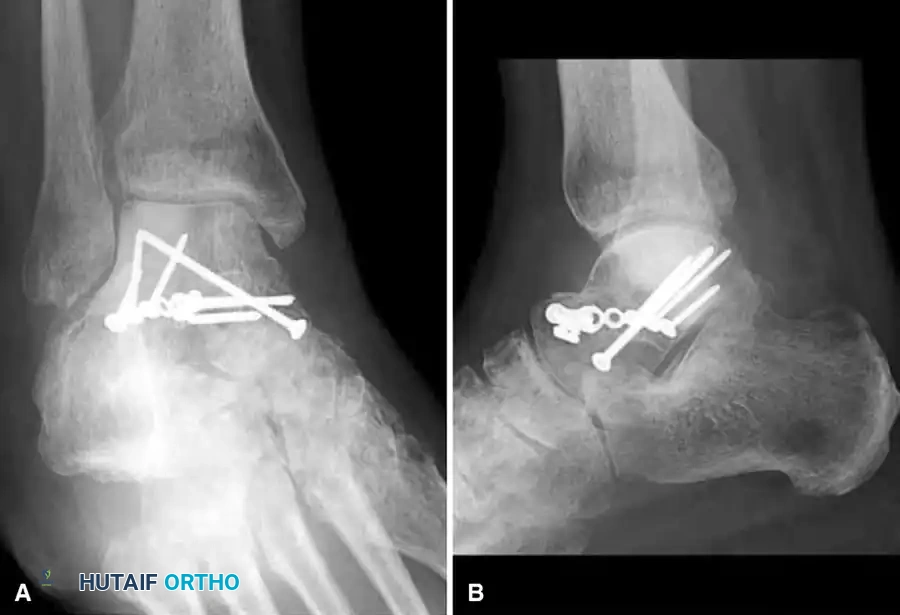

Definitive Fixation Strategies

Anterior-to-Posterior (AP) Screw Fixation:

* Depending on the available space for fixation, utilize 4.0-mm, 4.5-mm, or 6.5-mm partially threaded cannulated screws.

* Begin just posterior to the articular surface of the head on the medial or lateral aspect of the neck.

* Crucial Step: Care must be taken to countersink the screw head. This provides a flat area for seating and prevents impingement on the navicular articular surface.

Posterior-to-Anterior (PA) Screw Fixation:

* Place the guidewire above the lateral projection of the posterior process.

* Direct the wire anteriorly toward the lateral talar head.

* Fluoroscopic guidance is essential to avoid penetrating the subtalar joint.

Plate Fixation:

* Alternatively, minifragment plates (2.0 mm or 2.4 mm) and screws can be placed, especially if there is excessive comminution of the lateral neck or limited space for fixation in the head fragment. Plates act as a buttress against varus collapse.

Final Verification

- Check the final position with intraoperative fluoroscopy.

- Obtain a Canale view to definitively rule out varus malreduction.

- If the medial malleolus was osteotomized, reduce it anatomically and fix it with two parallel partially threaded cancellous screws.